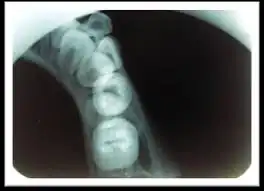

The body of the mandible may show irregular lucent/opaque changes with subperiosteal opaque layering along inferior border. It is a chronic osteomyelitis with subperiosteal bone and collagen deposition. There is no suppuration and sinus formation. It was first described by the Swiss surgeon Carl Garré.